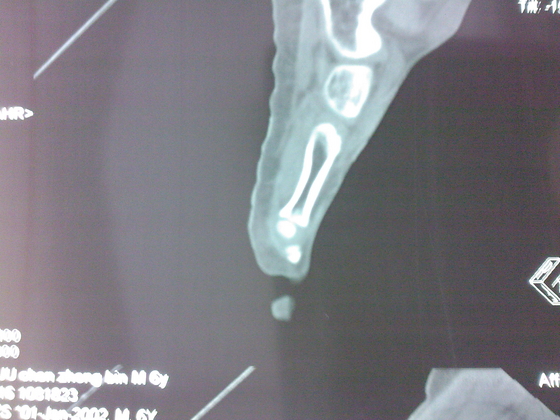

把病理送浙一医会诊后诊断为:骨外软骨瘤。同时做了CT检查。暂未予治疗。

今天把创面情况跟CT发上请大家看看。

继续发CT片

继续还有几张。